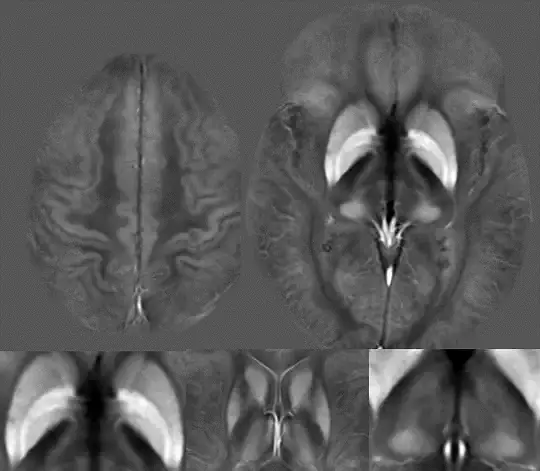

Dr. Schweser is one of the pioneering developers of Quantitative Susceptibility Mapping (QSM), a sophisticated MRI technique that allows for the quantification of magnetic susceptibility in the brain and other organs. This technology was developed at the Medical Physics Group led by Dr. Jürgen Reichenbach. Magnetic tissue susceptibility MRI provides a unique opportunity to assess tissue iron in a clinical setting. Dr. Schweser's pioneering work has opened up a new avenue of exploration in the medical field.

Iron is an essential co-factor in various biochemical pathways. Its deprivation from glial cells in the normal-appearing white matter is a pathological hallmark of multiple sclerosis that has been implicated in neuronal injury. It was recently observed that the thalamus of patients with multiple sclerosis shows a progressive decline in magnetic susceptibility. Other research suggests that a similar phenomenon may exist in other deep gray matter regions.

We are currently undertaking a comprehensive investigation into the population and subject-level dynamics of iron homeostasis imaging markers in the deep gray matter (DGM) of individuals with multiple sclerosis (MS). Our research aims to determine whether disease progression is associated with iron-related oligodendroglia dysfunction in the DGM. We anticipate that this research will have a significant impact on the field, as it will open up new avenues for the development of effective treatments to combat the progression of MS, ultimately improving public health.